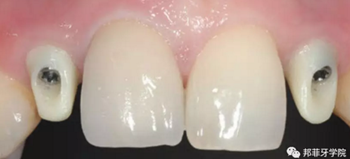

最終印模采用個(gè)性化印模柱,記錄穿齦輪廓(圖13)。CAD/CAM個(gè)性化基臺(tái)精確就位(圖14)。全瓷冠水門(mén)汀固位(圖15)。

圖 15-1:六個(gè)月后復(fù)查

圖 15-2:六個(gè)月后復(fù)查